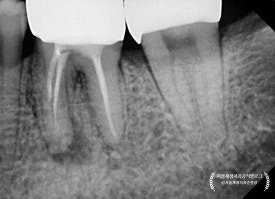

치근단 엑스레이를 살펴보겠습니다.

신경치료 후에 크라운으로 치아를 보호해주지 않고,

빈 구멍만 메워둔 상태로 몇년이 지났다고 합니다.

(프랑스에서 오신 환자분들은 대부분 크라운을 하지 않고 오시더군요. 식습관의 차이인지, 의료시스템의 차이인지...궁금합니다)

구멍을 메꾸는 재료만으로는

어금니의 씹는 힘을 충분히 견디기가 힘듭니다.

시간이 지남에 따라 재료가 마모되고 깨지면서

입 안의 세균들이 다시 치아 내부로 침투하게 되지요.

때워놓은 재료가 오래되어

하방으로 충치가 생기고 있었습니다.

신경치료 받은 치아에 충치가 다시 생긴다는 것은,

어금니 신경치료에 들인 공이 와르르 무너지는 것과 같습니다.

어금니의 신경치료 후

크라운으로 치아를 보호해주는 것은

자연 치아를 오래 쓰기 위한 필수조건입니다!